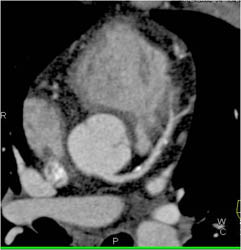

Diagnosis

Patent LAD